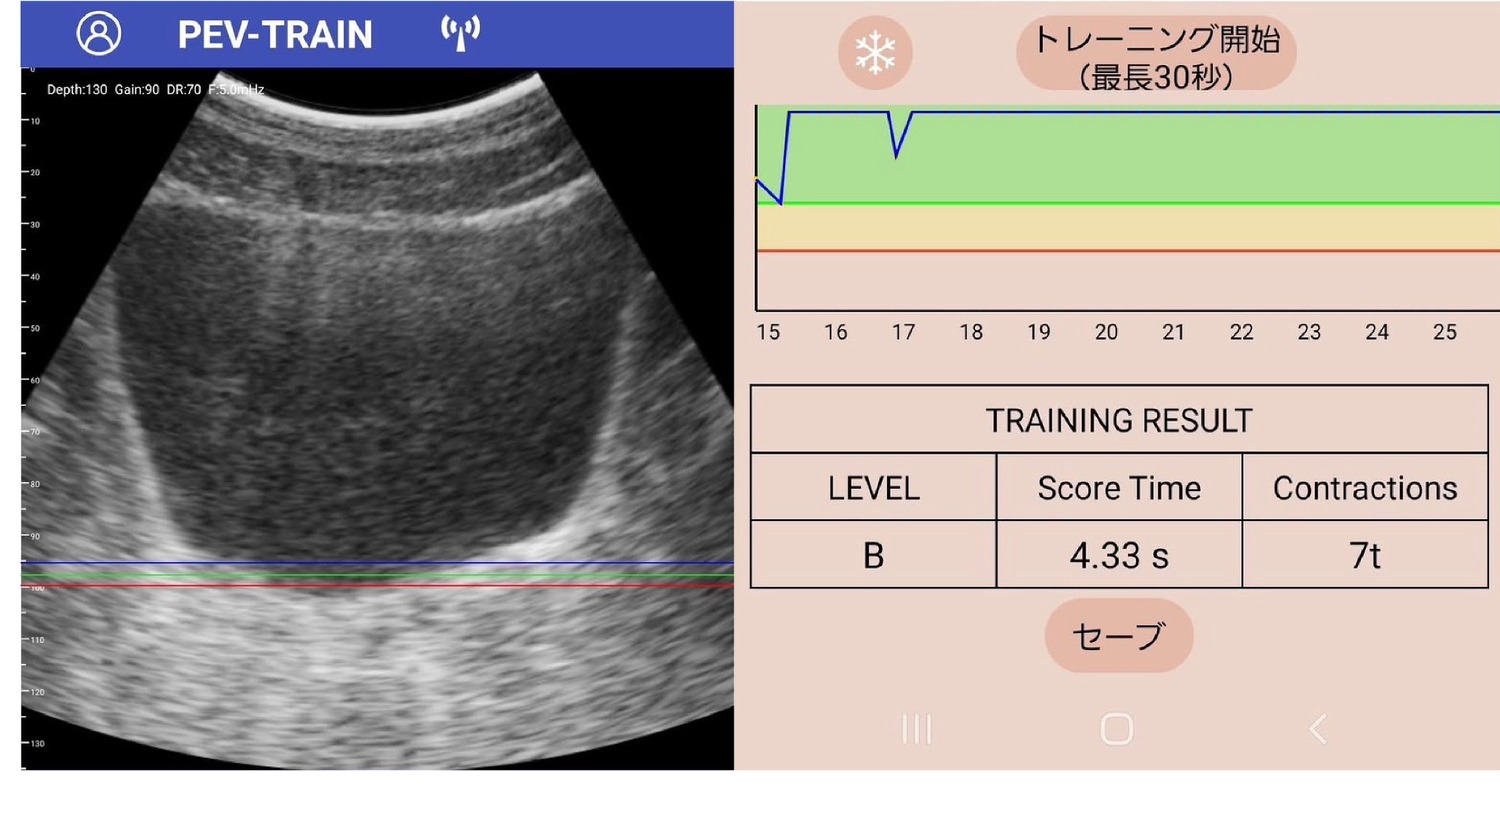

正しくトレーニングが行えているか分からない、どのくらい筋力が増えたのか効果が見えにくいといった従来の課題に対し、「PEV・TRAIN -ぺブトレ」は、ポータブル超音波エコーとスマホアプリが連動することで、誰でも簡単・正確にトレーニングできる新しい仕組みを提供。

主な特徴として、スマホで自分の骨盤底筋の動きを見ながらトレーニングが可能で、ポータブルエコーとアプリが連動し視覚的に確認できます。また、アプリが自動で効果を計測し、「収縮幅」「収縮時間」を自動レコーディングするのでトレーニング成果を一目で把握できます。

結果はその場で画面表示、効果をすぐに確認可能